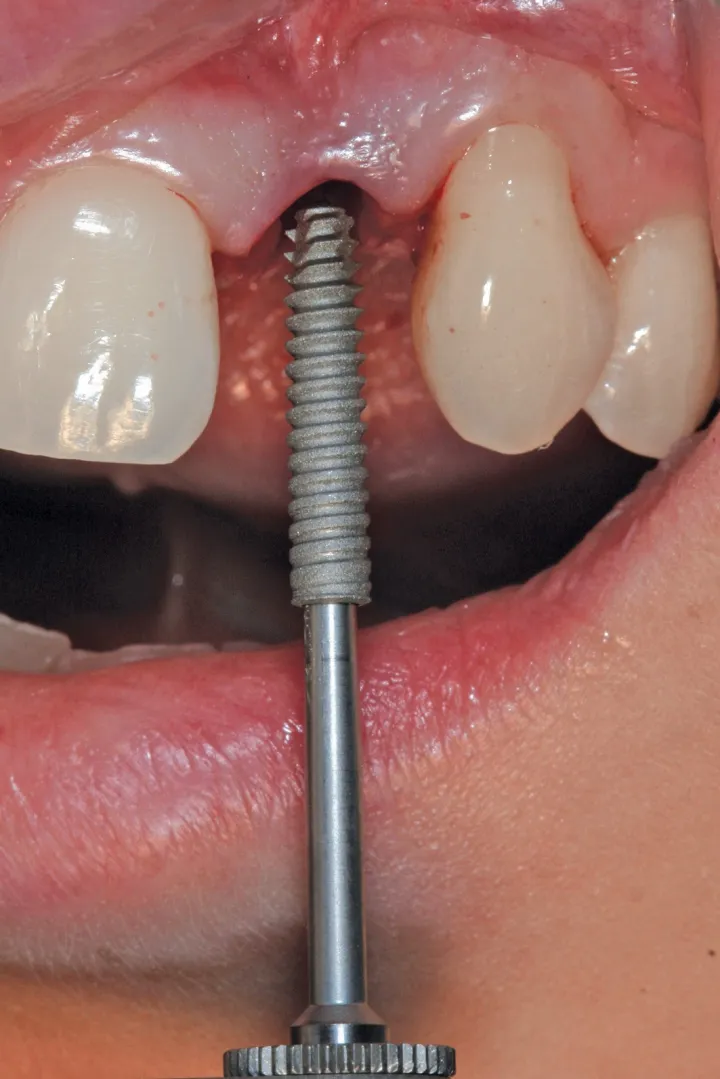

图 24 :植入 Axiom® 2.8 x 14 种植体。

图 25 :种植体就位。